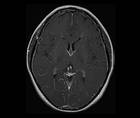

Case Report: New-Onset Headache With Tinnitus and Orthostatic Dizziness

Ryan P. CoburnRyan P. Coburn - Headache & Pain